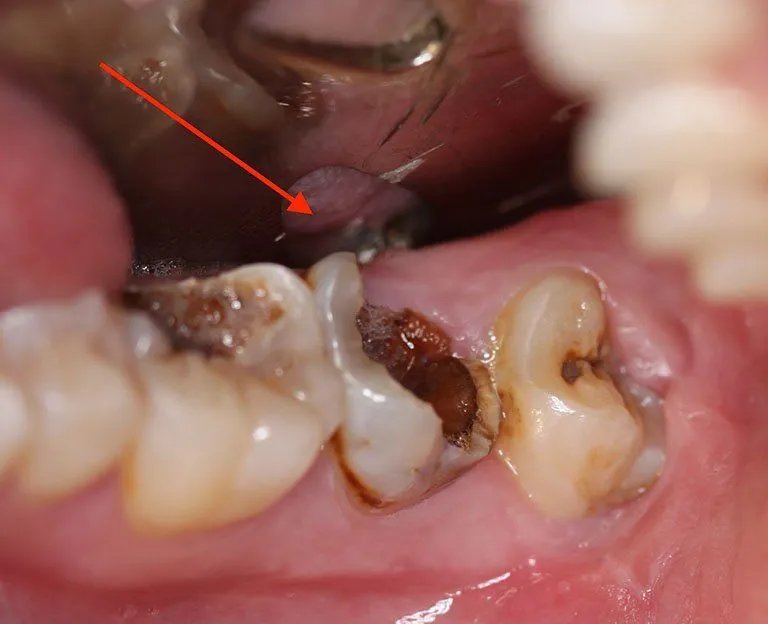

- Răng sâu nặng: Đặc trưng bởi các lỗ sâu lớn, rõ ràng trên răng, gây đau nhức liên tục, đặc biệt khi nhai hoặc cắn thức ăn. Răng có thể bị sứt mẻ, đổi màu và xuất hiện các triệu chứng viêm nhiễm như sưng nướu. Ở giai đoạn này, sâu răng đã xâm nhập sâu vào bên trong răng, đe dọa đến tủy răng.

Răng đổi màu, có lỗ sâu lớn: Răng bị sâu nặng thường bị đổi màu, trở nên sẫm màu hơn so với các răng khác. Bạn có thể nhìn thấy các lỗ sâu lớn, rõ ràng trên bề mặt răng. Răng cũng có thể bị sứt mẻ, vỡ vụn.